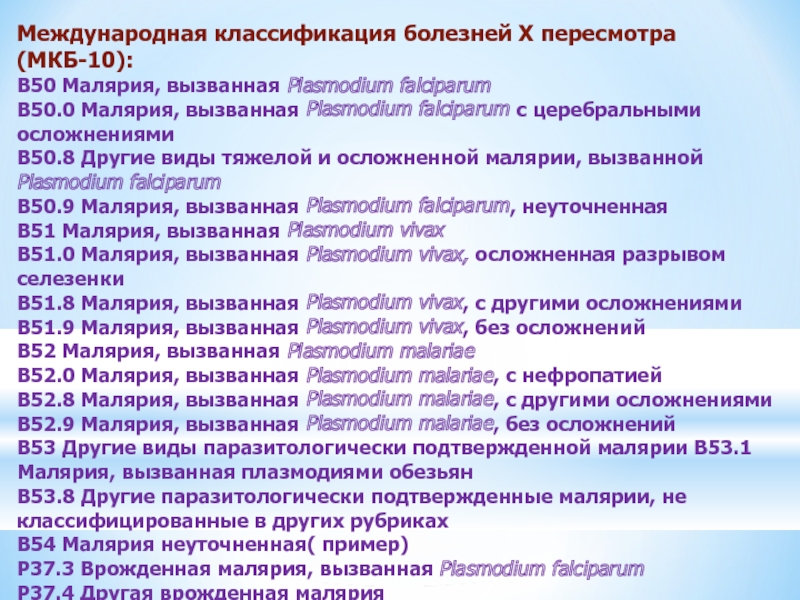

Острая внебольничная пневмония по МКБ-10: признаки и примеры